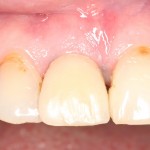

которая через три месяца, к моменту интеграции импланта, выглядит совсем иначе:

Ну и… к моменту установки постоянной коронки, у нас сохранился естественный контур прилегающей десны.

Что, собственно, нам и требовалось сделать.